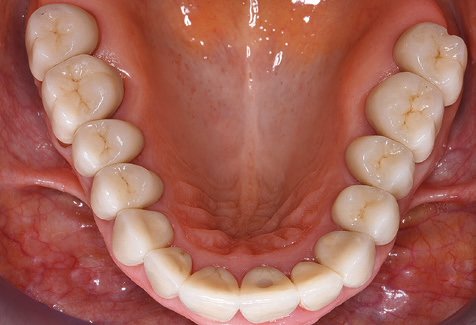

Eine 52-jährige Patientin stellte sich nach Zahnverlust im 3. Quadranten erstmals 2004 vor. Sie hatte den Wunsch nach einer prothetischen Neuversorgung. Im Rahmen der parodontologischen und radiologischen Diagnostik zeigte sich ein ausgeprägter parodontologischer Behandlungsbedarf. Die Zähne 48, 28, 27 zeigten zudem eine infauste Prognose und wurden entfernt (Abb. 1). Nach der erfolgreich abgeschlossenen systematischen PARTherapie wurde eine festsitzende implantatprothetische Versorgung mit Insertion von fünf Implantaten in Regio 35, 36, 37 und 46, 47 durchgeführt. Die prothetische Versorgung der natürlichen Zähne erfolgte mit verblendeten Zirkonoxidkeramikkronen, die Implantate wurden mit zweiteiligen individuellen Zirkonoxidabutments und ebenfalls verblendeten Kronen aus einer Zirkonoxidkeramik versorgt (Cercon base colored, Dentsply Sirona Lab). Die definitive Insertion der prothetischen Versorgung erfolgte im Jahr 2005.

Aufgrund der bestehenden parodontalen Vorerkrankung erfolgte die unterstützende Parodontaltherapie (UPT) in den ersten Jahren in einem DreiMonatsIntervall. Dabei zeigte die Patientin eine hohe Motivation und gute Compliance. Bei den jährlich erhobenen Sondierungsbefunden zeigten sich stabile parodontale Verhältnisse mit einem BOPIndex unter fünf Prozent. Aufgrund der stabilen parodontalen Situation und der guten Mitarbeit der Patientin wurde ab dem sechsten Jahr der prothetischen Funktionsphase das Recallintervall auf halbjährlich umgestellt. Auch mit diesem veränderten Recallintervall zeigten sich bei der jeweils jährlichen Aufnahme des Parodontalstatus stabile parodontale Verhältnisse, ohne Zunahme der Sondierungstiefen und einem BOPIndex unter fünf Prozent (Abb. 2a und b).

Im Rahmen der ZehnJahresKontrolle zeigten sich keine Hinweise auf einen fortschreitenden parodontalen Attachmentverlust oder einen periimplantären Knochenverlust (Abb. 3).